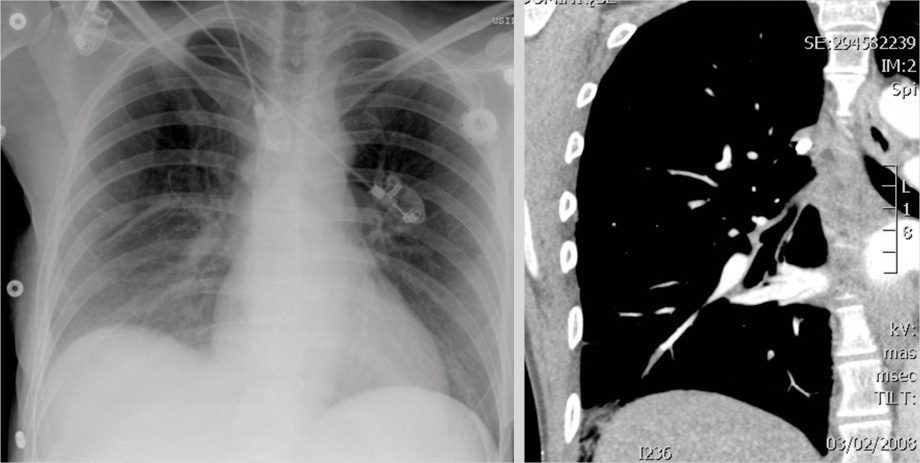

Embolie pulmonaire

Aspects radiologiques de l'embolie pulmonaire : ascension de coupole diaphragmatique.